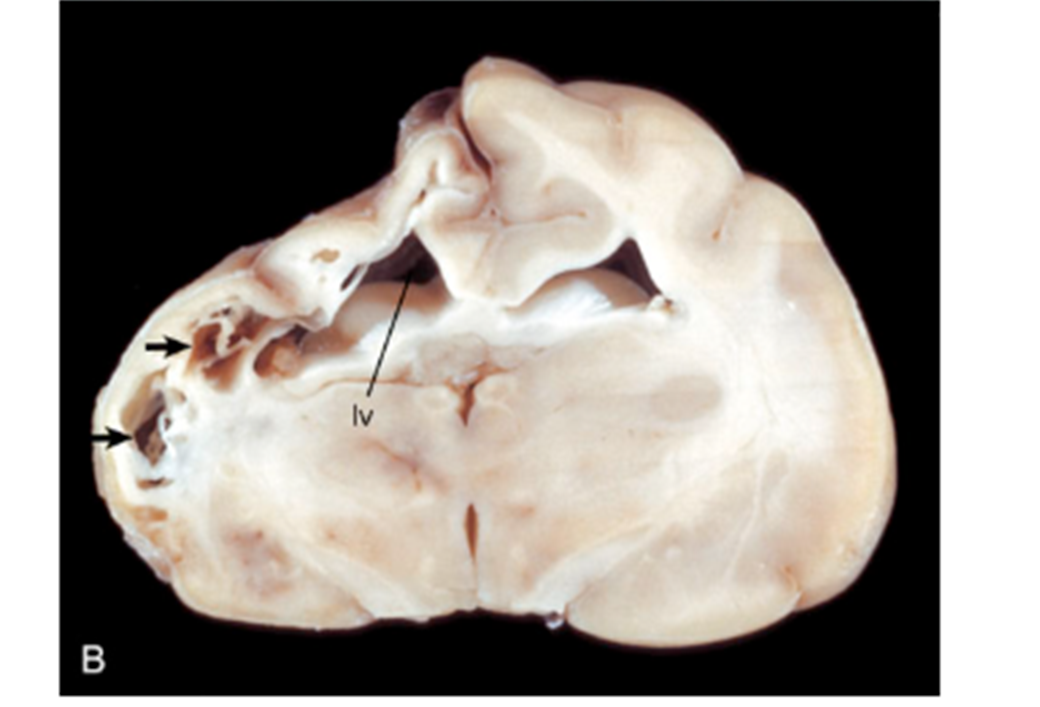

What pathology is shown in this image?

Focal symmetric encephalomalacia associated with Clostridium perfringens